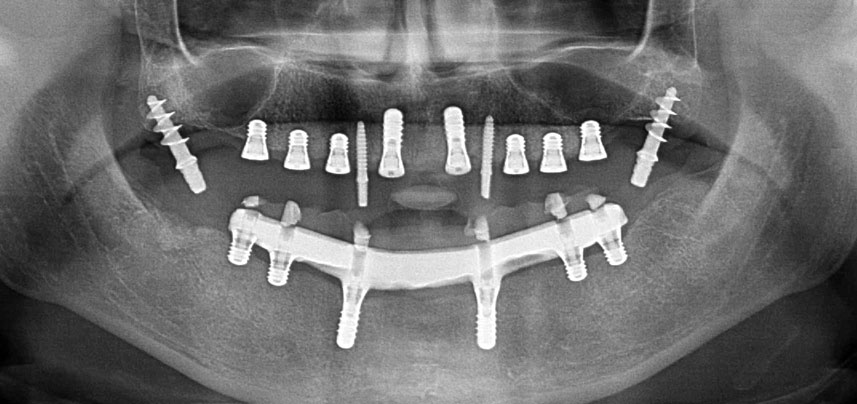

Une patiente de 41 ans sans particularités systémiques a perdu toutes ses dents à la suite d’une parodontite et de caries. Elle a finalement dû porter un appareil complet s'appuyant sur la muqueuse des deux mâchoires, s'accompagnant d’importantes difficultés masticatoires dues au mauvais ajustement des prothèses. La patiente a décidé de se faire poser, dans la mandibule, des implants destinés à supporter une prothèse CAD/CAM fixe retenue par une barre.

Trois ans après, le moment était venu pour elle de se doter d’une prothèse maxillaire du même type. Sur la base de la planification CBCT, l’élévation sinusale a été évitée grâce à la pose d'implants courts, et un gabarit chirurgical a été utilisé pour transférer les positions planifiées sur la crête alvéolaire (Figures 1 et 2).

Compte tenu de la dureté relative de l’os (D2) à cet endroit, les sites recevant des implants de 10mm de long aux régions 11 et 21 ont été finalisés à l'aide d’une fraise de 4mm de diamètre, associée à un contre-angle chirurgical W&H WS-75 L, au moteur d'implantologie Implantmed de W&H ainsi qu’au module Osstell ISQ de W&H. En revanche, en raison de leur structure osseuse molle, les sites postérieurs ont été préparés en vue de l’obtention d’un diamètre final de 3mm à l'aide de l’insert Piezomed I3P. Les implants ont enfin été posés par voie transgingivale (Flap Less) pour obtenir l’ostéointégration dans un délai de trois mois (Figures 6-10). L'appareil existant a été maintenu sur quatre implants provisoires (Fig. 8).